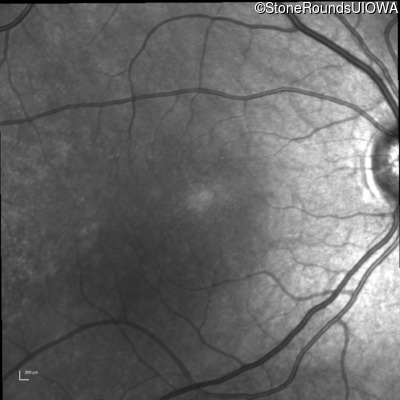

Infrared Fundus Photograph - Right - 20/32 -2 sc

Exemplar